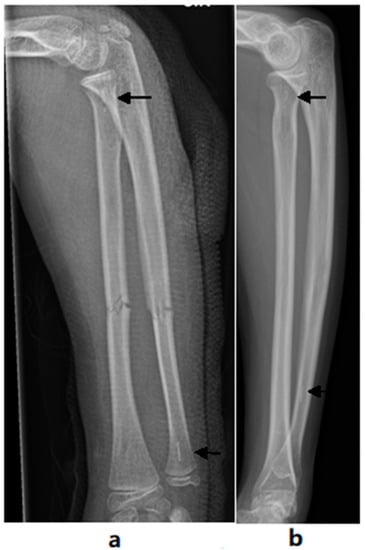

The PLGA implants of the BIN group were completely absorbed in 15 out of 26 bones (58%, 95% CI 37% to 77%) and almost completely absorbed in 11 bones, according to the MR images. The nail residuals appeared as faint, linear, low-signal short markings (Figure 2). The nail canal disappeared completely in 20 (77%, 95% CI 56% to 91%) forearm bones and almost completely in six bones. These residual canals demonstrated higher signals than the cancellous bone in the T1 and T2 images of the MRI. In two out of all 26 bones, thin nail residuals were found to be surrounded by a 3–4 mm halo effect (Figure 3). The tri-calcium-phosphate marker at the end of the nail was visible in 24 out of 26 (92%, 95% CI 76% to 98%) forearm bones in the MR images. (Table 3) The formation of intraosseal cysts was not detected.

Figure 2. T1-weighted axial images showing low-signal biodegradable nails (white arrows) one month postoperatively (a) and faint nail residuals 6.5 years postoperatively (b).

During the long-term follow-up period, i.e., a mean of 6.8 years after the surgical treatment with biodegradable intramedullary nailing, the fixation material was completely absorbed in more than half of the bones (15/26, 57.7%) and almost completely absorbed in 11 out of 26 (42.3%) bones upon MRI. The remaining small particles of the nails were thin and faint at the long-term follow-up (Figure 2). This is rather different from previous short-term findings at the two-year mark, at which the nails were all visible [30]. Even though the resorption time was longer than previously suspected, the finding supports the use of the study method. In the present study, there were no complications related to the degradation process, such as cysts or osteolysis. However, the finding may encourage further development of the implant material to undergo a more rapid degradation process.